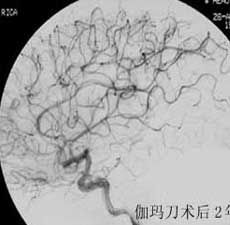

----立体定向放疗(γ-刀、χ-刀)对AVM是一种有希望的选择性治疗方法。据文献报道,AVM治疗后年消失率30%~50%,2年消失率70%~90%,其消失速度与所用的照射量成正比,与AVM的大小成反比。从治疗到AVM完全闭合之前每年的出血率3%~4%,与自然出血史相同,所以对有出血史的患者,应优先采用栓塞或手术方法。大型AVM经若干次栓塞后体积缩小即可放射治疗。但栓塞物质应是NBCA。其它颗粒或丝线栓塞,均有复发之虞。栓塞加立体定向放疗可使60%~80%的患者免于开颅手术而获治愈。

----立体定向放疗(γ-刀、χ-刀)对AVM是一种有希望的选择性治疗方法。据文献报道,AVM治疗后年消失率30%~50%,2年消失率70%~90%,其消失速度与用的照射量成正比,与AVM的大小成反比。从治疗到AVM完全闭合之前每年的出血率3%~4%,与自然出血史相同,所以对有出血史的患者,应优先采用栓塞或手术方法。大型AVM经若干次栓塞后体积缩小即可放射治疗。但栓塞物质应是NBCA。其它颗粒或丝线栓塞,均有复发之虞。栓塞加立体定向放疗可使60%~80%的患者免于开颅手术而获治愈。